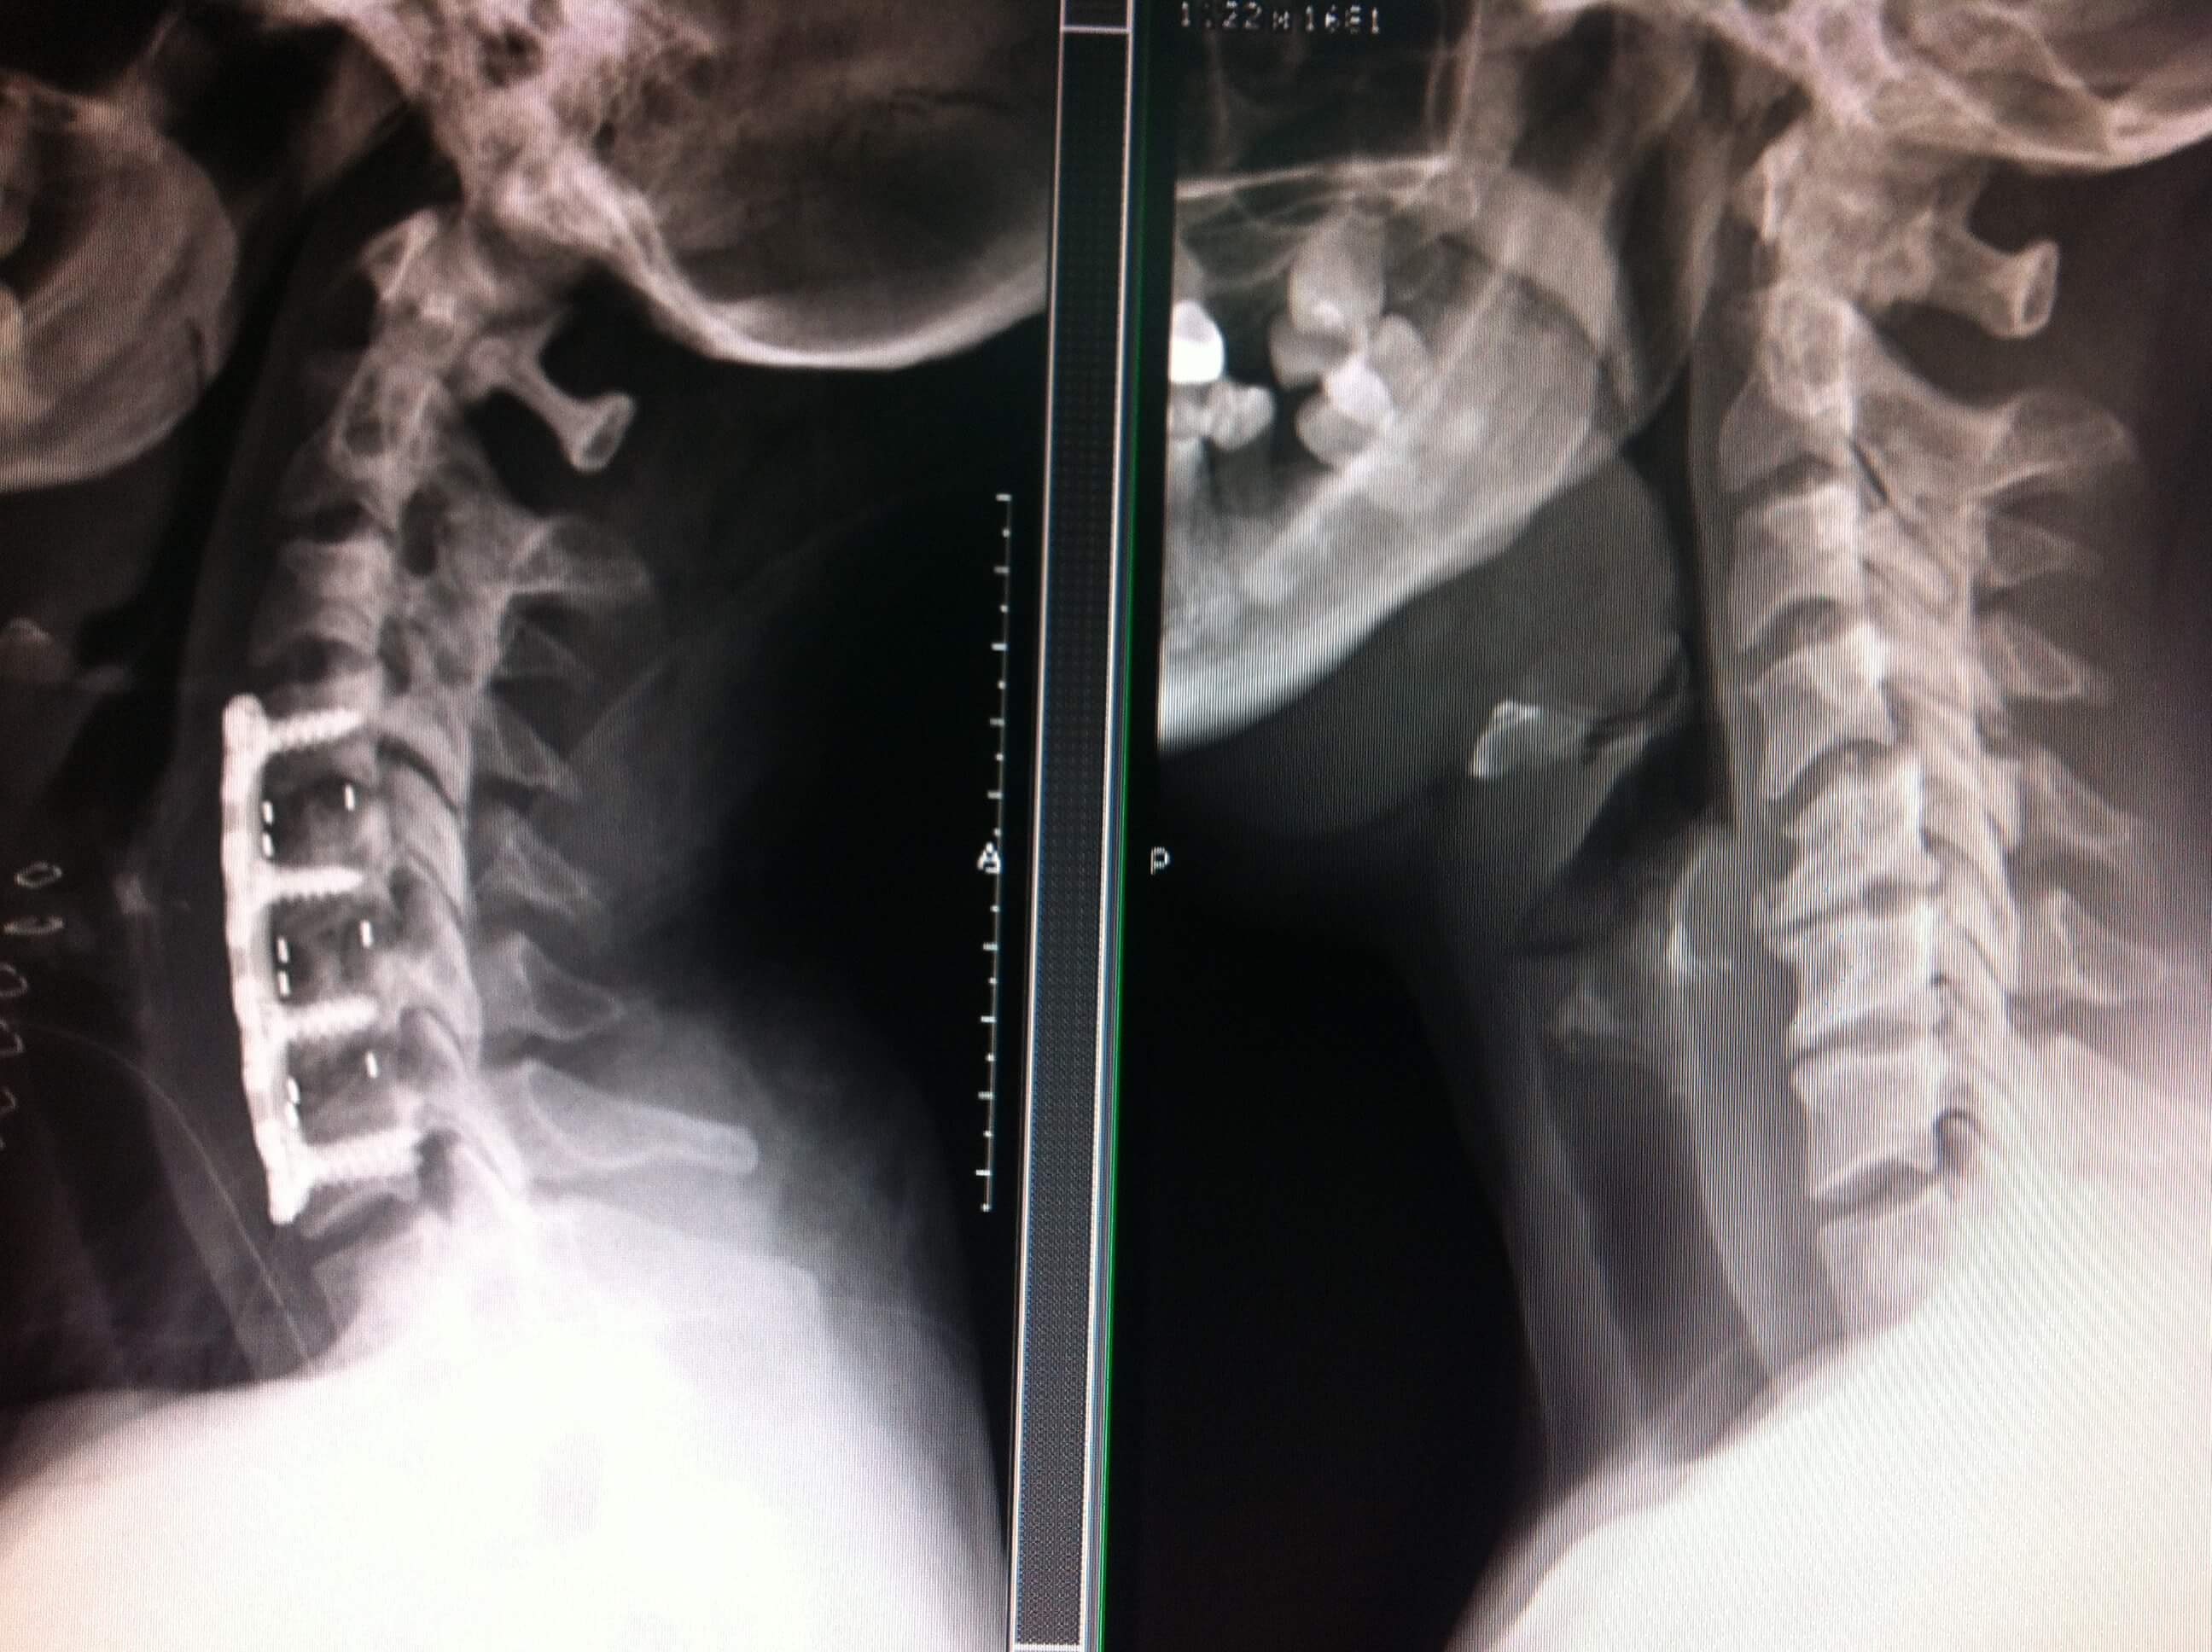

WebConsejos para el postoperatorio de artrodesis lumbar 1-Pasee: paseos cortos y frecuentes Camine cada día cortas distancias y auméntelas cada día de manera progresiva.. WebLa columna cervical, región anatómica donde se origina esta patología, está formada por siete vértebras y discos intervertebrales, y el desgaste se crea en las articulaciones. WebJunto a la rehabilitación,para que la evolución sea favorable a largo plazo,es importante que el paciente conozca, que debe evitar levantar pesos excesivos,ya que es una de las. WebTendrá que usar una ortesis (corsé) después de la cirugía para mantener estable la columna y promover la cicatrización durante 2 meses. En cama podrá retirarla. Se tarda. WebLa artrodesis cervical posterior no requiere quitar el disco intervertebral, para realizar la fusión vertebral usaremos tornillos y barras. COMPLICACIONES DE LA. WebSi la hernia era cervical entenderá que tampoco podrá trabajar de forma inmediata por lo que quizás tendrá que usar analgésicos y opiáceos que le evitarán.

WebLa artrodesis cervical posterior no requiere quitar el disco intervertebral, para realizar la fusión vertebral usaremos tornillos y barras. COMPLICACIONES DE LA. WebSi la hernia era cervical entenderá que tampoco podrá trabajar de forma inmediata por lo que quizás tendrá que usar analgésicos y opiáceos que le evitarán.